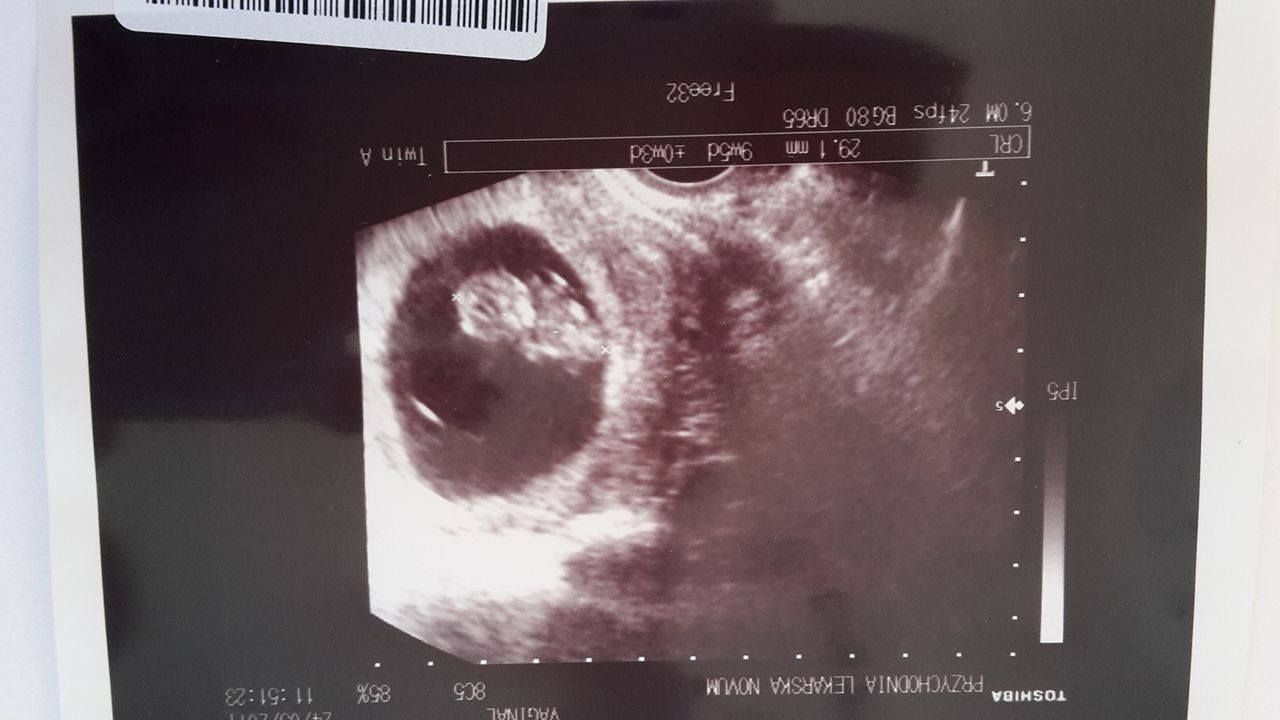

Wczoraj miałam wizytę z usg, niestety wieści po niej częściowo dobre a częściowo nie. Jedno serduszko przestało nam bić, ale na szczęście drugi bąbelek rozwija się prawidłowo. Mimo iż wizyta była smutna to byłam dumna z mojego bąbelka, który skakał i nie dał się uchwycić. Chyba nie lubi zdjęć i ma to po mamusi.

A o to i on. Zobacz załącznik 807941

09.06.2017 mam badania prenatalne, namawiają mnie też na test PAPPA głównie ze względu na tego bąbelka który znikł.